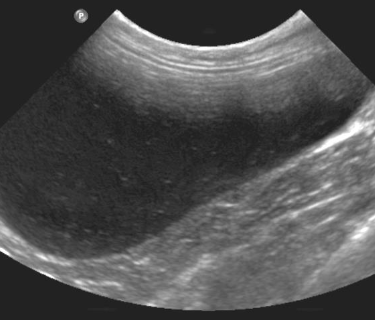

8 - Quels organes sont visualisables ici ?

A - La Vessie

B - Le Foie

C - La Vésicule biliaire

D - La prostate

E - La Rate

F - Le canal cystique

G - Le canal cholédoque

9 - Sur cette même image échographique que pouvez-vous dire ?

A - J'observe la présence d'un calcul biliaire

B - Je n'observe aucune anomalie

C - J'observe la présence d'une mucocoele biliaire

D - J'observe la présence d'une cholangite

E - J'observe la présence d'une cholécystite

Question 8 : Réponses B,C,F,G

Question 9 : Réponses D, E